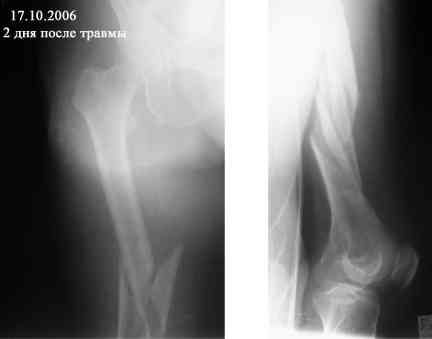

В продолжение темы оскольчатого перелома бедренной кости.

Р-граммы в динамике

Уважаемый Александр! Спасибо за предложение по устройству больной. Каким образом вы могли бы помочь я не вижу. Больная из г. Евпатории Крым, Украина, как я уже писал неимущая. В нашем отделении такие операции не делаются (хотя есть ЭОП - единственный в Крыму). Заведующий на оперативное лечение больной почему-то не настроен. По-моему несращение ей обеспечено, завтра зайду к ней - проверю (52 дня на вытяжении!). Вопрос - что с ней делать дальше если на операцию не идут? Выгнать с ложным суставом домой умирать? Или лежать до самой смерти (близкой) на вытяжении - я понимаю - человек ко всему привыкает но не до такой же степени. Кстати - сопутствующее у нее сросшийся чрезнадмыщелковый перелом левой плечевой кости (травма и операция (открытая репозиция, МОС спицами) в мае 2006 года).